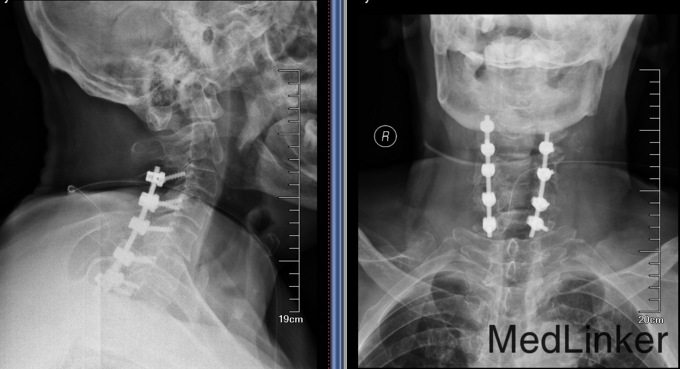

患者男,81岁,自述于1个月前出现双上肢感觉减退,发胀,以左侧为重,后来加重,左侧握力减退,于201医院就诊,行颈椎MR检查,提示为颈3-4、4-5间盘突出,为求进一步治疗就诊于我院,患者病来饮食、睡眠佳。大小便正常,体重无明显变化。

诊断:颈椎病,颈椎间突出,高血压病 患者入院后完善相关检查,请相关科室及麻醉科会诊,医院医务部审批后,查无其他手术禁忌症,于全麻下行颈椎后路单开门椎管扩大减压侧块螺钉内固定术。术后给予患肢雾化祛痰,抗炎,消肿,营养神经,接骨等对症治疗。术后患者在颈领的保护下可下地行走,术后14天拆线后予以出院,